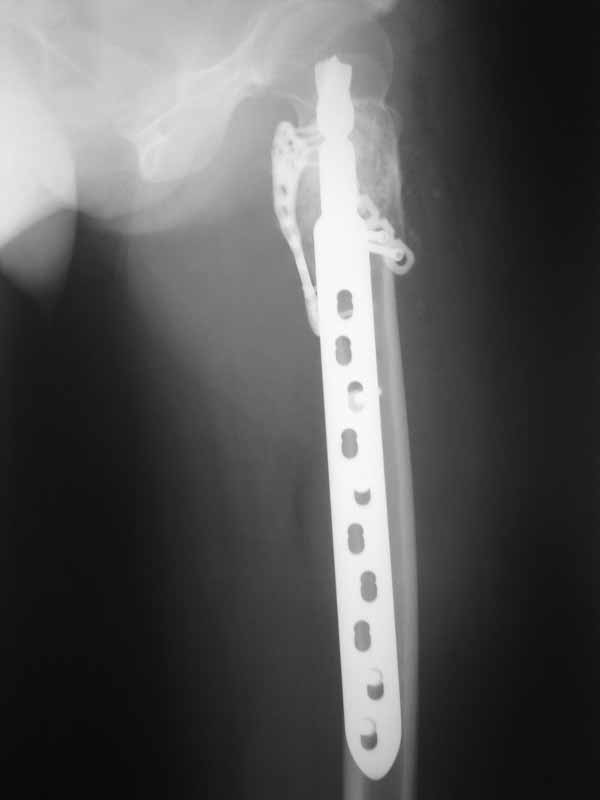

Молодая пациентка 23 лет. Травма в результате падения с высоты своего роста. Упала 2 дня назад доставлена к нам вот с такой картиной. Из анамнеза - боли беспокоят в течении полугода, постоянные. Никуда не обращалась. Уважаемое сообщество подскажите - ОБК?, Фиброзная дисплазия?, Киста?. Тактика ведения?. Девушка молодая!!!

А по пациентке:Обследования провели в легких чисто, лабораторно - без особенностей. Выполнили МРТ - костная киста, однокамерная. Оперирована - створчатая остеотомия, удаление кисты, костная пластика аутокостью с гребня подвздошной кости, остеосинтез DHS со сприральным клинком, створка фиксирована пластинами монокортикально.

Макроскопически - слизеподобное содержимое темно-бурого цвета, отдали на гистологию.